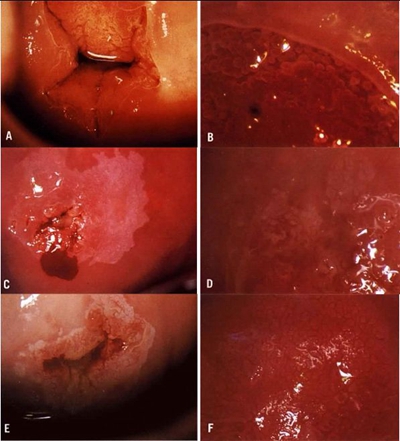

子宮頸癌圖片

宮頸癌

宮頸癌

宮頸癌

宮頸癌

宮頸癌

宮頸癌

宮頸癌

宮頸癌

宮頸癌

宮頸癌

宮頸癌

宮頸癌

宮頸癌

宮頸癌

宮頸癌

宮頸癌

宮頸癌

宮頸癌

宮頸癌

宮頸癌